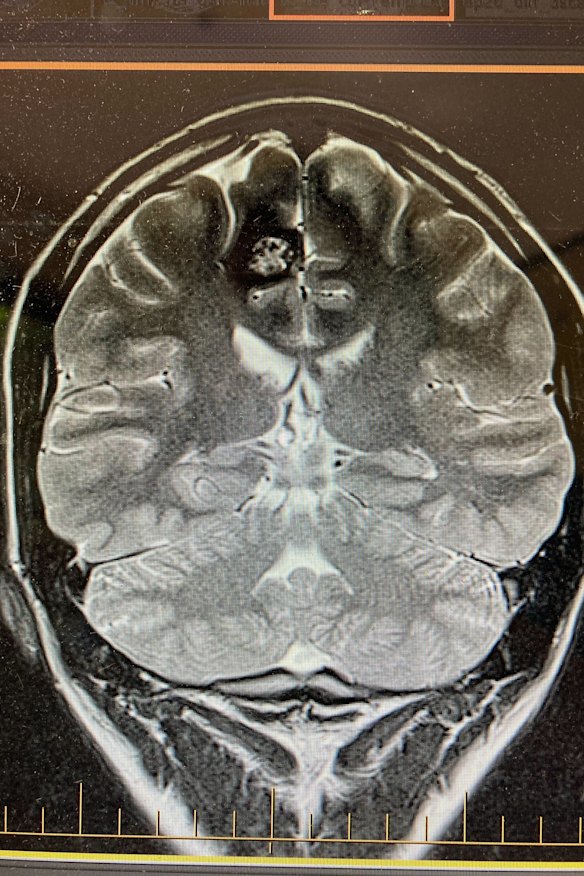

The tremors had begun in my hand; the ring and the little finger, twitching as if pulled by invisible strings. When they progressed into full arm convulsions, an MRI confirmed the culprit: a non-cancerous, raspberry-sized formation of blood vessels called a cavernoma. Within two weeks I had an appointment with one of Drummond’s neurosurgical colleagues at the Royal Melbourne, who gave me two options: take anticonvulsant medication for the rest of my life, or get it removed for good.

A scan of Angus Thomson’s brain showing the cavernoma at top left, which was causing his hand to shake uncontrollably.Credit: